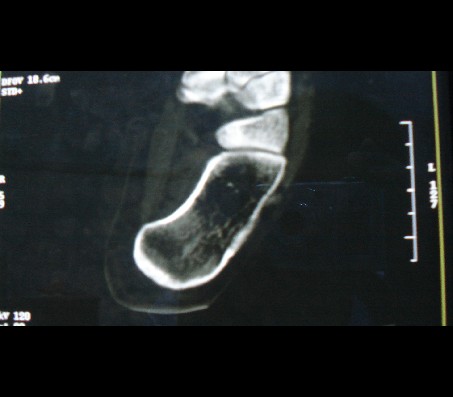

标题: CT15130:女性,24岁,左跟骨疼痛,X线发现小片状高密度影,C [打印本页]

标题: CT15130:女性,24岁,左跟骨疼痛,X线发现小片状高密度影,C

跟骨前方低密度ct值-60hu